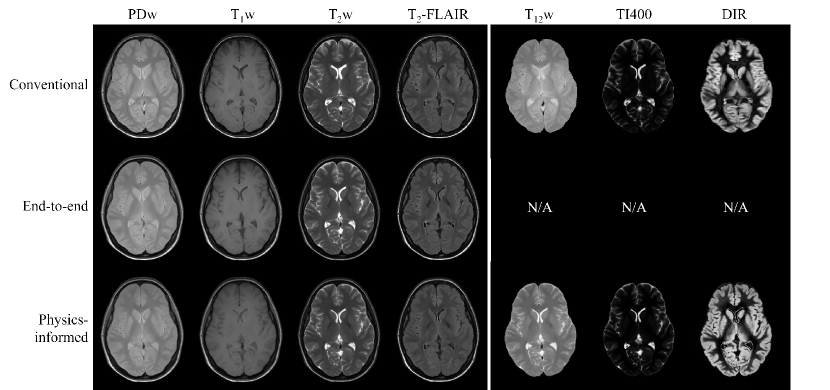

The standard end-to-end approach can only synthesize contrasts seen during training. Contrarily, the experiment results suggest that the physics-informed approach can synthesize any desired contrast from the q*-maps (Fig. 7). Similar to the T1w contrast, the physics-informed synthetic T12w has a hyperintense CSF compared to the conventional T12w contrast. For the physics-informed synthetic TI400 and DIR contrasts, the signal suppression is almost identical to the ground truth contrasts, although slight hyperintensities can be observed in the WM of the synthetic DIR contrasts. The CNR values of the synthetic T12w and TI400 contrasts were close to the values of their respective ground truths: 2.65 0.12 versus 2.24 0.21 and 56.9 11.4 versus 54.8 7.96, respectively. The CNR values of the synthetic DIR contrast were considerably lower than for its ground truth: 12.8 3.31 versus 17.6 1.79.